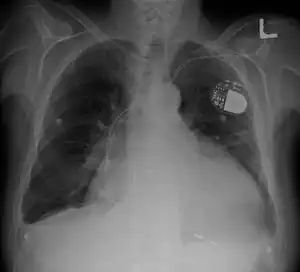

| Cardiomegaly on chest X-ray with a pacemaker | |

- Chest X-ray: X-ray images help to visualize the condition of the lungs and heart. If the heart is enlarged on an X-ray, other tests will usually be needed to find the cause. A useful measurement on X-ray is the cardio-thoracic ratio, which is the transverse diameter of the heart, compared with that of the thoracic cage.[24] These diameters are taken from PA chest x-rays using the widest point of the chest and measuring as far as the lung pleura, rather than lateral skin margins. If the ratio is greater than 50%, pathology is suspected.[25] The measurement was first proposed in 1919 to screen military recruits. A newer approach to using these x-rays for evaluating heart health takes the ratio of heart area to chest area and has been called the two-dimensional cardiothoracic ratio.[26]